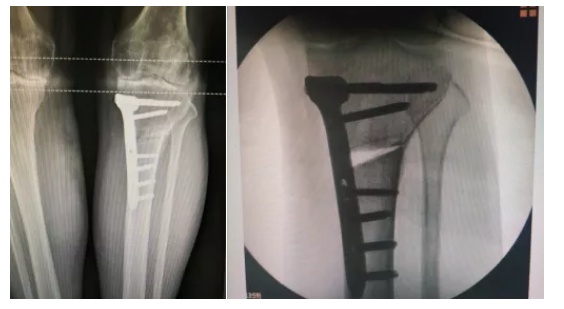

③ 保膝:是一种旨在通过纠正局部骨骼形状来改变整个下肢力线的手术。年纪很轻,膝关节磨损比较局限,但力线已经发生了明显改变,医生可能会建议您先做“截骨保膝”手术。截骨术不是永久性的,以后可能需要进一步手术。

④ 单髁置换术:对于只是膝关节内侧髁磨损,外侧髁依然完好的患者,单髁置换手术将是更好的选择。这种人工关节保留了外侧髁、髌骨、交叉韧带等结构,与传统的全膝关节置换术相比,提供更多的生理功能、更大的活动范围、以及更快的术后恢复。